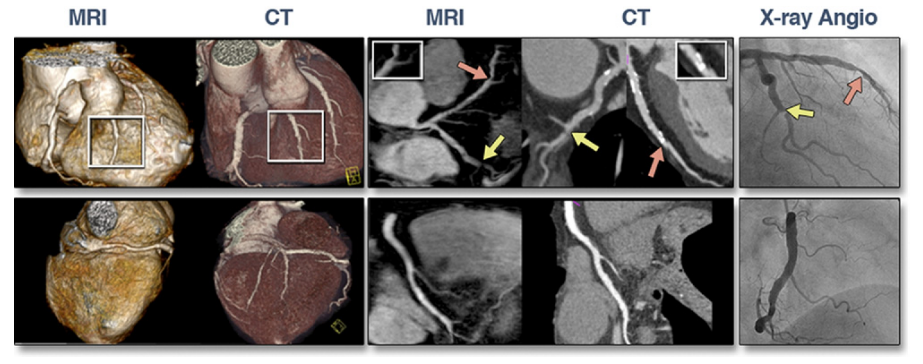

以下図1に、同一症例のMRI, CT, CAG画像(文献[2]より引用)を示す。左側2列はMRI, CTいずれもVolume Renderingという3D再構成された画像である。その右側2列の白黒の画像は、MRI・CTのmultiplanar reconstruction (MPR) 画像、および最右列はCAG画像である。右3列の赤色矢印・黄色矢印はそれぞれ前下行枝・回旋枝の同じ病変を示し、特に赤色矢印は石灰化病変のモダリティの違いによる見え方の違いが示される。

図1 同一症例のMRI, CT, CAG画像  文献[2] より引用

図1. 同一症例のMRI, CT, CAG画像 (文献[2]より引用)